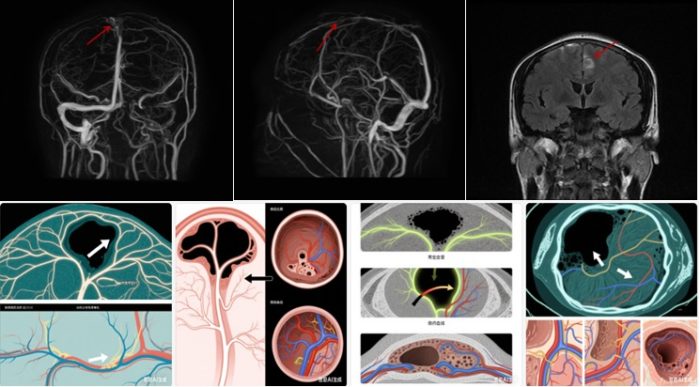

颅内静脉窦是大脑特有的“静脉回流枢纽”,由硬脑膜折叠形成不规则腔隙,主要包括上矢状窦、横窦、乙状窦、直窦等,相互连通成网状(图 1)。其核心功能有两点:一是收集大脑静脉血经颈内静脉回流心脏;二是吸收脑脊液,维持颅内液体平衡。正常情况下,静脉窦内血流通畅,如同城市地下排水系统持续排出“代谢废水”。

而 CVST 是指颅内静脉窦内形成血凝块堵塞管腔,导致静脉血回流受阻、脑脊液吸收障碍。这类似排水管网被淤泥堵塞:静脉血淤积引发脑组织水肿,脑脊液吸收受阻导致颅内压升高;若堵塞持续,可能撑破脑内细小静脉引发“静脉性脑出血”,甚至因脑水肿压迫脑干危及生命。(图2)

MRI:可直接显示脑水肿、静脉性脑出血,还能识别静脉窦内血栓——急性期(1周内)血栓T1加权像呈“高信号”,T2 加权像呈“低信号”;亚急性期(1-4周)T1、T2 加权像均呈“高信号”,易于识别。

MRV:显示静脉窦血流情况,正常静脉窦呈“高信号亮线”,血栓堵塞部位呈 “信号缺失区”,还可显示侧支循环(图3)。

DSA是诊断CVST的“金标准”,通过导管注射造影剂动态显示静脉窦血流,可精准看到血栓位置、范围、侧支循环(图4)。但它是有创检查(需穿刺血管),仅在MRI/MRV诊断不明确或需介入治疗时使用。